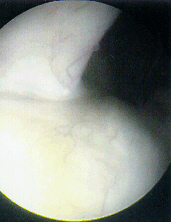

Diagnostic Arthroscopy- Indications

- Persistent pain and instability

- Recurrent effusions

- Obvious ACL injury or meniscal tear by clinical exam